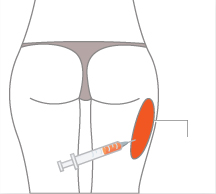

허벅지, 엉덩이 등에서

불필요한 지방을 채취합니다